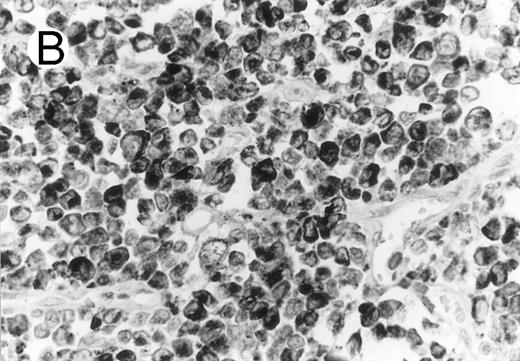

Cytotoxic granule antigen expression in a common form of ALCL (Table 2; case 11). (A) Immunostain for CD30 highlights sheets of large tumor cells. (B) The tumor cells of this case display granular cytoplasmic TIA-1 immunoreaction with paranuclear accumulation in the Golgi region. (C) Strong cytoplasmic perforin reaction is shown in the same case. (sABC-peroxidase technique, hematoxylin counterstain, original magnification × 400.)

Anaplastic large cell lymphomas of T-cell and ‘null’-cell type.The results are summarized in Tables 1 and 2. Twenty-three (70%) of the 33 ALCL cases revealed TIA-1 positivity in the lymphoma cells. In 20 of the 23 positive cases virtually all tumor cells were positive, while in the remaining 3 cases less than half of the tumor cells showed TIA-1 positivity. Sixteen TIA-1+ cases displayed a T-cell phenotype, six revealed a null-cell phenotype, and one had an ambiguous phenotype staining with both T-cell and NK-cell markers. Positive staining was seen in 13 out of 19 (68%) CS forms, and all (100%) of the 6 HR and 2 SCP variants. The typical staining pattern was granular and cytoplasmic, with frequent paranuclear staining in the Golgi region (Fig 1). The 2 SCP cases showed homogenous granular TIA-1 reaction in both the small cell and the CD30+ large cell components. In addition, 2 of the 3 AIDS-associated cases (67%) showed positive staining, whereas none of the 3 PC forms marked for TIA-1. Beside neoplastic cell staining, small reactive lymphocytes with a similar typical granular staining pattern were seen in all cases investigated. These lymphocytes represented scattered interfollicular and intrafollicular small cells, but in some cases accounted for up to 40% of the non-neoplastic paracortical lymphocytes either in the involved or uninvolved lymph node regions. Cytoplasmic TIA-1 staining also occurred in normal granulocytes, but with a less distinct granular pattern than in positive lymphocytes. In some cases, occasional epithelioid histiocytes displayed weak, diffuse cytoplasmic staining. TIA-1+ tumor cells revealed a distinct granular staining pattern that was always easily distinguishable from reactions of granulocytes and epithelioid histiocytes.